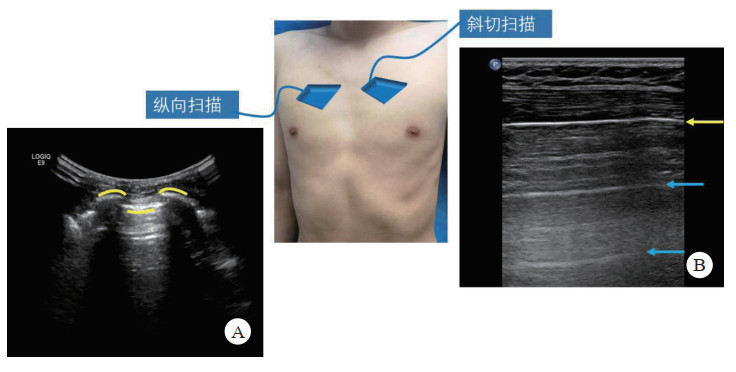

2.3.1 肺部超声基本表现 2.3.1.1 蝙蝠征将探头垂直放置于肋间,由胸膜线、上下肋骨构成形似蝙蝠的图像,是肺部超声检查的基本切面。(图 5-A)。

|

| A: 纵向肺扫查可见上肋骨、下肋骨(黄线)和胸膜线、A线组成状似“蝙蝠”的图像;B: 沿肋间隙扫查可见连续的胸膜线呈水平线(黄箭),后方为平行的、与皮肤到胸膜线等间距的A线(蓝箭) 图 5 肺部超声扫查 |

|

|

即超声波遇到胸膜的多重反射后形成的多条和胸膜平行的亮线。A线呈高回声,随距离衰减;平行于胸膜线;A线间等间距。正常的肺超声图像通常可见2-3条平行的A线(图 5-B)。

2.3.1.3 胸膜滑动征正常情况下,脏壁层胸膜紧贴,随呼吸相对滑动,在实时超声检查时可以观察到。

2.3.1.4 B线是超声波遇到肺内气体后形成的放射状彗尾伪像,从胸膜线发出,并随胸膜滑行而移动,不随着距离而衰减(图 6-A)。

|

| A: 肺水肿时出现B线,B线起源并垂直于胸膜线,呈放射状发散至肺野深部(箭头);B、C:血气胸时,胸腔可见液性暗区,并可见积液内高回声漂浮 图 6 肺部超声检查常见征像 |

|

|

是指在正常肺组织与气胸的病理性肺组织之间的过渡区会产生肺点征象。

2.3.2 肺部损伤的超声快速识别。(1)气胸:胸膜滑动征消失,出现肺点。

(2)血胸:如坐位扫查,仅肋膈角被无回声积液充填,为少量积液;如任意体位胸腔均可见液性暗区,为中-大量积液,超声对其诊断准确性100%[39](图 7-B)。

(3)肺水肿:可见大量B线。

2.3.3 检查方法采用BLUE法中的检查位置(见图 7)。共6个检查点:(1)上BLUE点位于上面手的中央(左侧、右侧共2个);(2)下BLUE点位于下面手掌的中央(左侧、右侧共2个)。这四个点遵循肺部解剖,尽可能避开了心脏;(3)后侧肺泡或胸膜综合征点(posterolateral alveolar and/or pleural syndrome point, PLAPS)位于下蓝点延长线与腋后线相垂直的交点;(4)膈肌点(diaphragmatic point)位于下蓝手小指外侧缘即膈肌线,其延长线与腋中线交点。检查时间一般不超过3 min。

检查时间一般不超过3 min。

|

| A: 上蓝点(2个)、下蓝点(2个);B:PLAPS点(黄箭)、膈肌点(蓝箭) 图 7 BLUE法定位扫查 |

|

|

【推荐意见4】肺部超声是E-FSAT检查中的一部分,也可根据具体临床情况单独进行,在对航天员进行肺部超声检查时,可采用Blue法定位,快速对血气胸及相关隐匿性胸部伤情进行筛查。